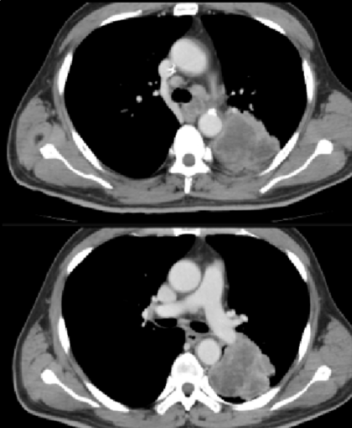

自2024年7月起,由卢冰教授率领贵州医科大学附属医院、附属肿瘤医院胸部肿瘤科团队和放射物理师团队率先开展SFRT的临床应用,至今已完成几十例患者的临床治疗。第1例应用SFRT治疗的患者由卢冰教授带领李青松副主任医师、胡银祥高级工程师完成。对一例LA-NSCLC患者在同期放化疗联合免疫维持治疗的标准治疗模式中,放疗采用SFRT,疗程结束时肿瘤明显缩小,定期随访发现肿瘤完全消失(图示),取得了远超常规放疗的临床效果,而且无明显的放疗并发症,病人生活质量满意,可自行驾车外出游玩。

治疗前

CT影像